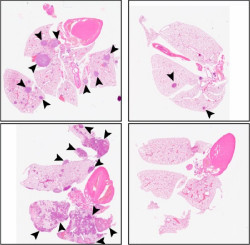

La bebidas edulcoradas con fructosa líquida aceleran la enfermedad del hígado graso por dietas altas en grasas

Una dieta rica en grasas no es suficiente para provocar la enfermedad del hígado graso a corto plazo. Ahora bien, si esta dieta se combina con el consumo de bebidas edulcoradas con fructosa líquida, se acelera la acumulación de grasas en el hígado y aparece un cuadro de hipertrigliceridemia, un factor de riesgo cardiovascular, según muestra una investigación de la Facultad de Farmacia y Ciencias de la Alimentación, el Instituto de Biomedicina de la Universidad de Barcelona (IBUB) y el CIBEROBN.